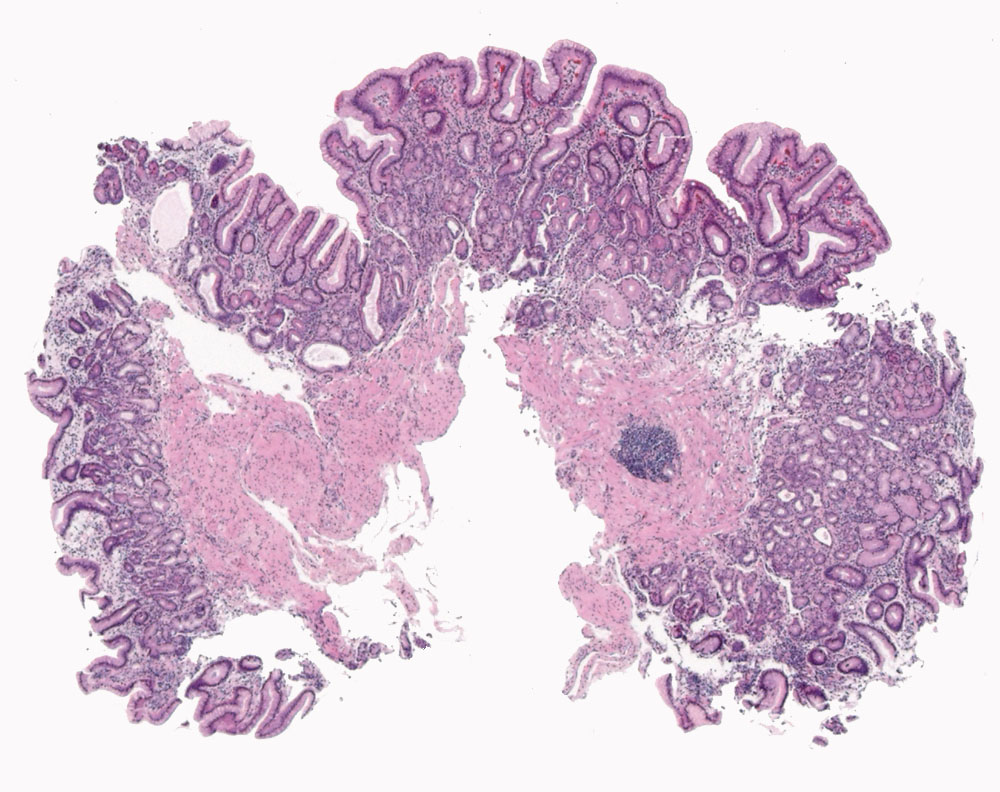

PathoPic – image database / PathoPic ID 10688 - Atrophe Gastritis (Typ A): pseudopylorische und intestinale Metaplasie

Atrophe Gastritis (Typ A): pseudopylorische und intestinale Metaplasie

Topographie

Magenkorpus

Beschreibung

Immunhistochemisch zeigt sich eine lineare Hyperplasie der endokrinen Zellen (ECL-Zellen) im Magenkorpus mit einem Antikörpercocktail gegen den neuroendokrinen Marker Chromogranin A. Dieser Befund unterstützt die Diagnose einer Typ A-Gastritis.

Anämieabklärung, kein Gewichtsverlust, keine Diarrhoe. NSAR. Verdacht auf atrophe Gastritis.

Histologie

25